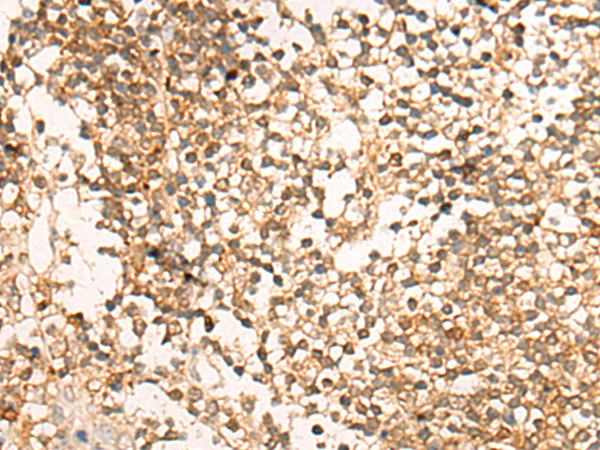

IHC positive control:

Human colorectal cancer and Human tonsil

IHC Recommend dilution:

20-100